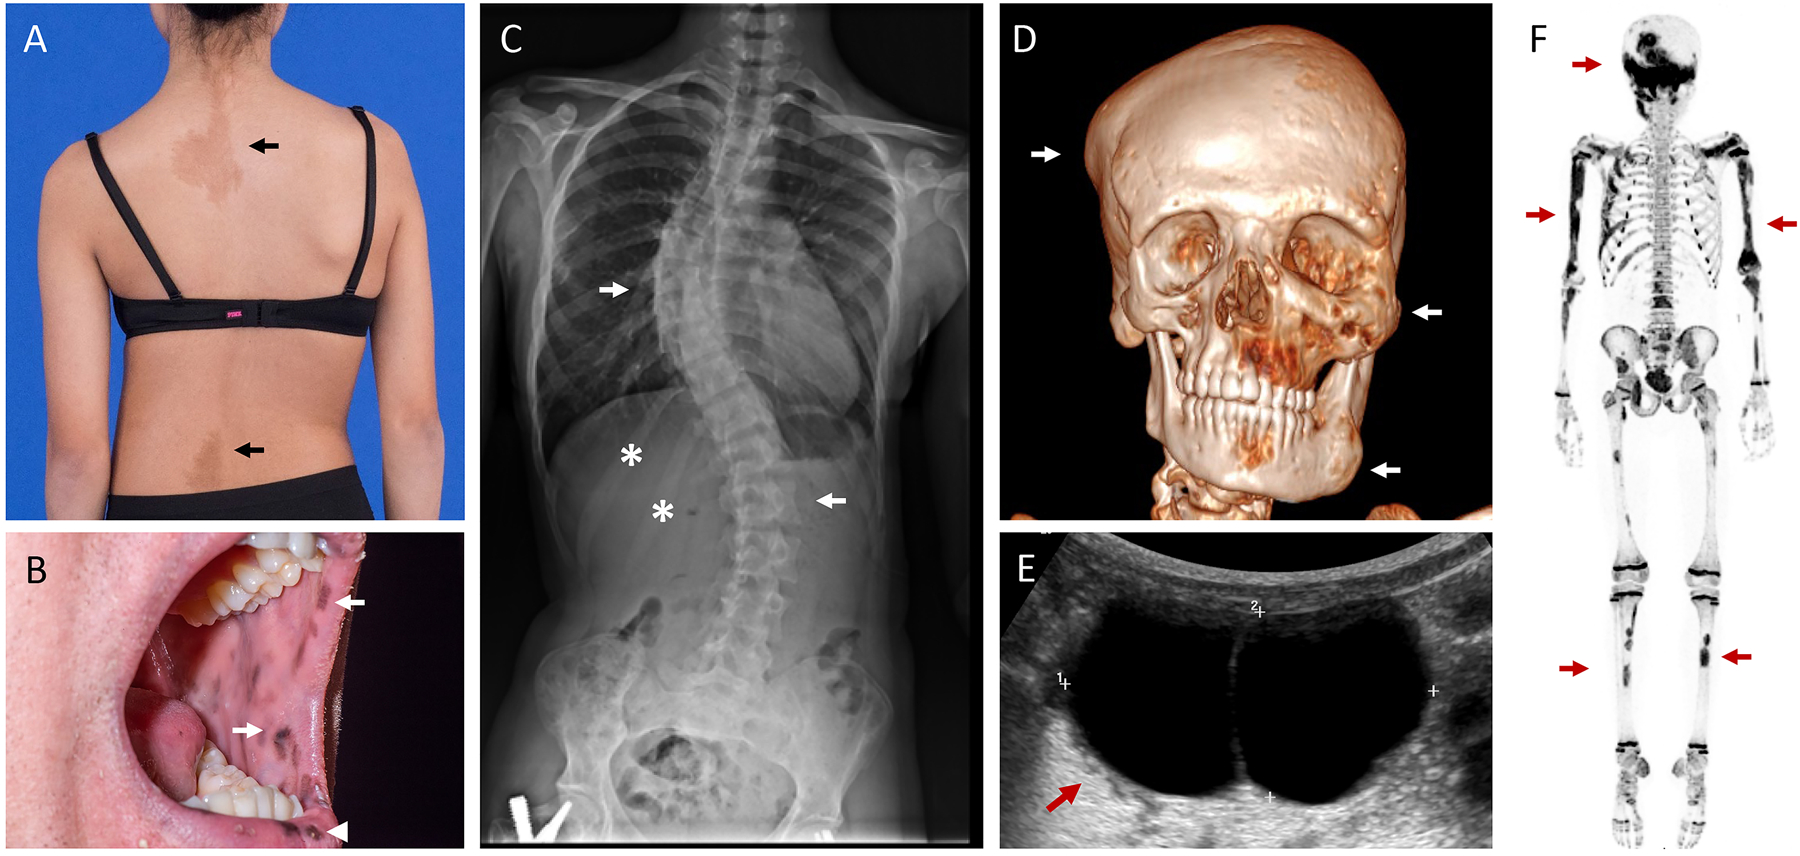

Figure 2.

Clinical images in Fibrous Dysplasia/McCune-Albright Syndrome. A. Café-au-lait macules reflect along the spine of an adolescent girl (arrows), demonstrating typical jagged borders and distribution along the midline of the body. Note the obliquity in this patient’s hips and shoulders, reflective of underlying scoliosis. B. Lentigines involving the oral mucosa (arrows) and outer lips (arrowhead) in an adult patient. C. Radiograph from the patient in panel A show severe scoliosis involving the thoracic and lumbar spine (arrows). Expansile FD lesions are apparent in the right 11th and 12th ribs (asterisks). The patient has a surgical implant visible in the proximal right femur related to a previous fracture repair. D. Three-dimensional computed tomography scan demonstrates multiple expansile FD lesions involving the calvarium, maxilla, and mandible (arrows). E. Pelvic ultrasound in a 3-year-old girl with pubertal symptoms and elevated estrogen levels reveals a large ovarian cyst (arrow). F. 18F-NaF PET/CT scan shows multiple areas of tracer uptake in the skull, ribs, spine, and long bones, consistent with polyostotic FD (arrows). Note the expected physiologic, symmetric uptake in the metaphyses throughout in this growing child.